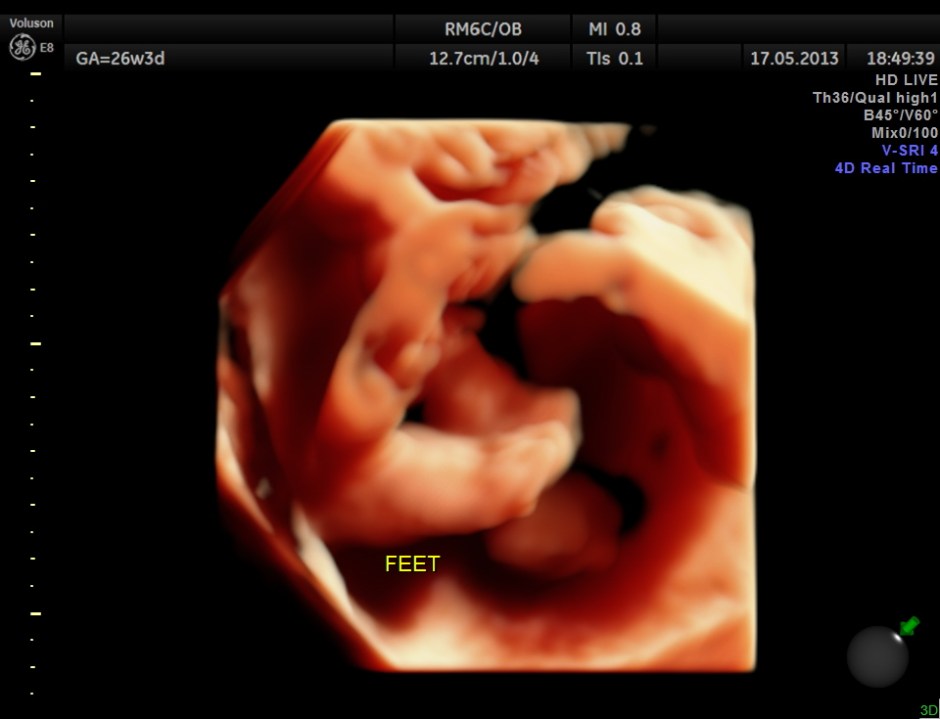

The limbs are shown below.